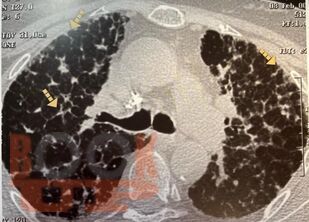

Гранулематозные заболевания легких

Гранулематозные заболевания легких : учебное пособие / И. В. Демко, Н. В. Гордеева, М. Г. Мамаева и др. - Красноярск : КрасГМУ, 2022. - 167 c. - Текст : электронный // ЭБС "Букап" : [сайт]. - URL : https://www.books-up.ru/en/book/granulematoznye-zabolevaniya-legkih-19634258/ (дата обращения: 19.04.2026). - Режим доступа : по подписке.

Учебное пособие предназначено для врачей общей практики, участковых терапевтов, аллергологов, пульмонологов. В настоящем учебном пособии освещены принципы ведения пациентов с диссеминированными заболеваниями легких. Обсуждаются вопросы этиологии, патогенеза, диагностики, а также основные методы лечения.